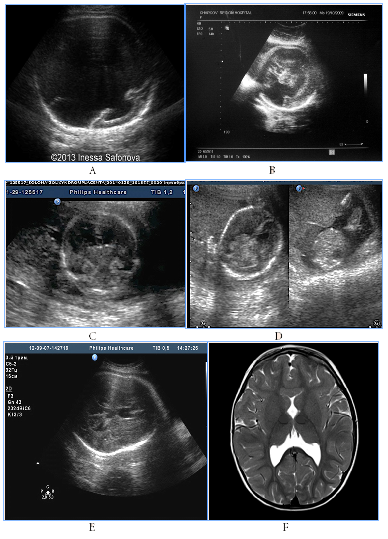

All cases with prosencephalic malformations had an adverse catamnesis connected with combined pathology. Two cases of alobar holoprosencephaly (HPE) and syndromic semilobar HPE were connected with perinatal losses. Syndromic lobar HPE with partial callosal agenesis and septo-optic dysplasia didn't have perinatal consequences, but the clinical outcome for the child was unfavorable as well (Figure1). HPE in 3rd trimester, 4 cases:

Figure 1 HPE in 3rd trimester, 4cases.

А) Alobar syndromic HPE with the residual mantle of the cortex at the base of the brain, severe progressive disgenetic hydrocephalus with macrocrania, intranatal death, clinical intranatal mismatch of head and pelvic size, fetus-damaging operation.

B) Isolated alobar HPE, cup-shaped type, the biggest part of the cortical mantleis attended, but it does not cover a single ​​anterior ventricular area, infant death.

C, D, E). Semilobar syndromic HPE with callosal agenesis. The ventricles are connecting through a narrow channel across the midline, thalamuses partially fused, IUGR, absent umbilical end-diastolic flow, antenatal death.

F). Fetal NSG and MRI of the newborn with syndromic lobar HPE, partial callosal agenesis, septo-optic dysplasia, US variant with merged, widely separated narrow acute-angled anterior horns of ventricular and dilated Verga’s cavity, long-term neurological disorders, severe visual impairment, epilepsy in the kid.